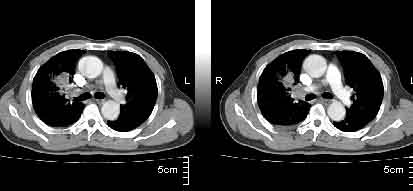

该病例我的诊断意见:右肺上叶周围型肺癌伴纵隔和右肺门淋巴结增大和右肺上叶阻塞性肺炎{病灶周围致密影以近肺门侧明显!}。右侧少量胸腔积液。

一. 1)症状有无发热及慢性过程.2)化验室检查?3)有无tb接触史?二.右肺上叶见片团状影,边界欠清,外侧方见一结节状软组织影,密度欠均匀,内可见低密度坏死区.周围强化明显,肺内见纤维索条影,局部胸膜增厚,但无明确胸膜凹陷.上叶支气管壁增厚,肺门及纵隔淋巴结增大.右侧胸腔少量积液.诊断意见:1右肺上叶慢性感染性疾病(肺tb?)伴肺门,纵隔淋巴结大.右胸少量积液.右肺上叶结节影多为tb球?2右肺上叶周围型肺ca伴肺门,纵隔淋巴结转移待排.右肺上叶炎变(肺门及纵隔淋巴结压迫).右胸少量积液.等待随返结果.